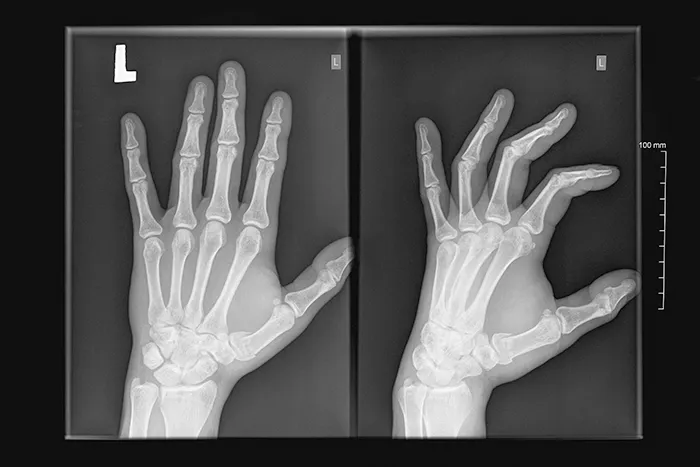

손가락 통증을 일으키는 원인 중 하나인 방아쇠 수지는 손가락이 딱 소리가 나면서 통증이 동반되는 증상이 있으며, 손가락을 펴거나 구부릴 때 통로에 걸리는 느낌으로 방아쇠를 당기 듯한 느낌과 손가락을 펼 때 튕기듯 펴지는 증상이 있습니다.

방아쇠 수지는 손가락의 관절 부근에서 통증이 발생하는 증상이에요. 특히 손가락을 움직일 때, 마치 방아쇠를 당기는 듯한 느낌이 들거나 손가락이 갑자기 튕기는 느낌이 있어요.

손가락을 펴거나 구부릴 때 통증이 생기고, 그 부위가 부을 수 있어요. 증상이 심해지면 손가락이 구부러져서 움직이지 않을 수도 있어요. 아침에 일어나면 증상이 더 나쁘다가 시간이 지나면 조금 나아질 수 있어요.

증상이 아주 심할 때에는 손가락이 구부러진 상태에서 고정되는 경우도 있습니다.

방아쇠 손가락은 손가락으로 가는 힘줄이나 힘줄이 지나가는 피막에 염증이 생겨서 발생합니다

힘줄에 염증이 생기면서, 그리고 점점 염증이 진행되면서 힘줄이 지나는 통로에 걸려서 이런 증상이 나타나게 됩니다.